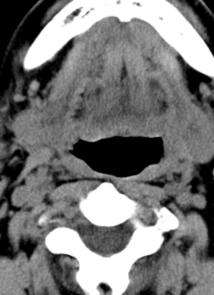

标题: CT17168:会诊,颈部包块 [打印本页]

标题: CT17168:会诊,颈部包块

怎么不传病史呢?右侧颌下腺炎症?

考虑:右侧颌下腺炎症。建议强化。

不排除右侧颌下腺恶性肿瘤可能;建议行进一步检查。

考虑:右侧颌下腺炎症可能。

我也是报的颌下腺炎症。